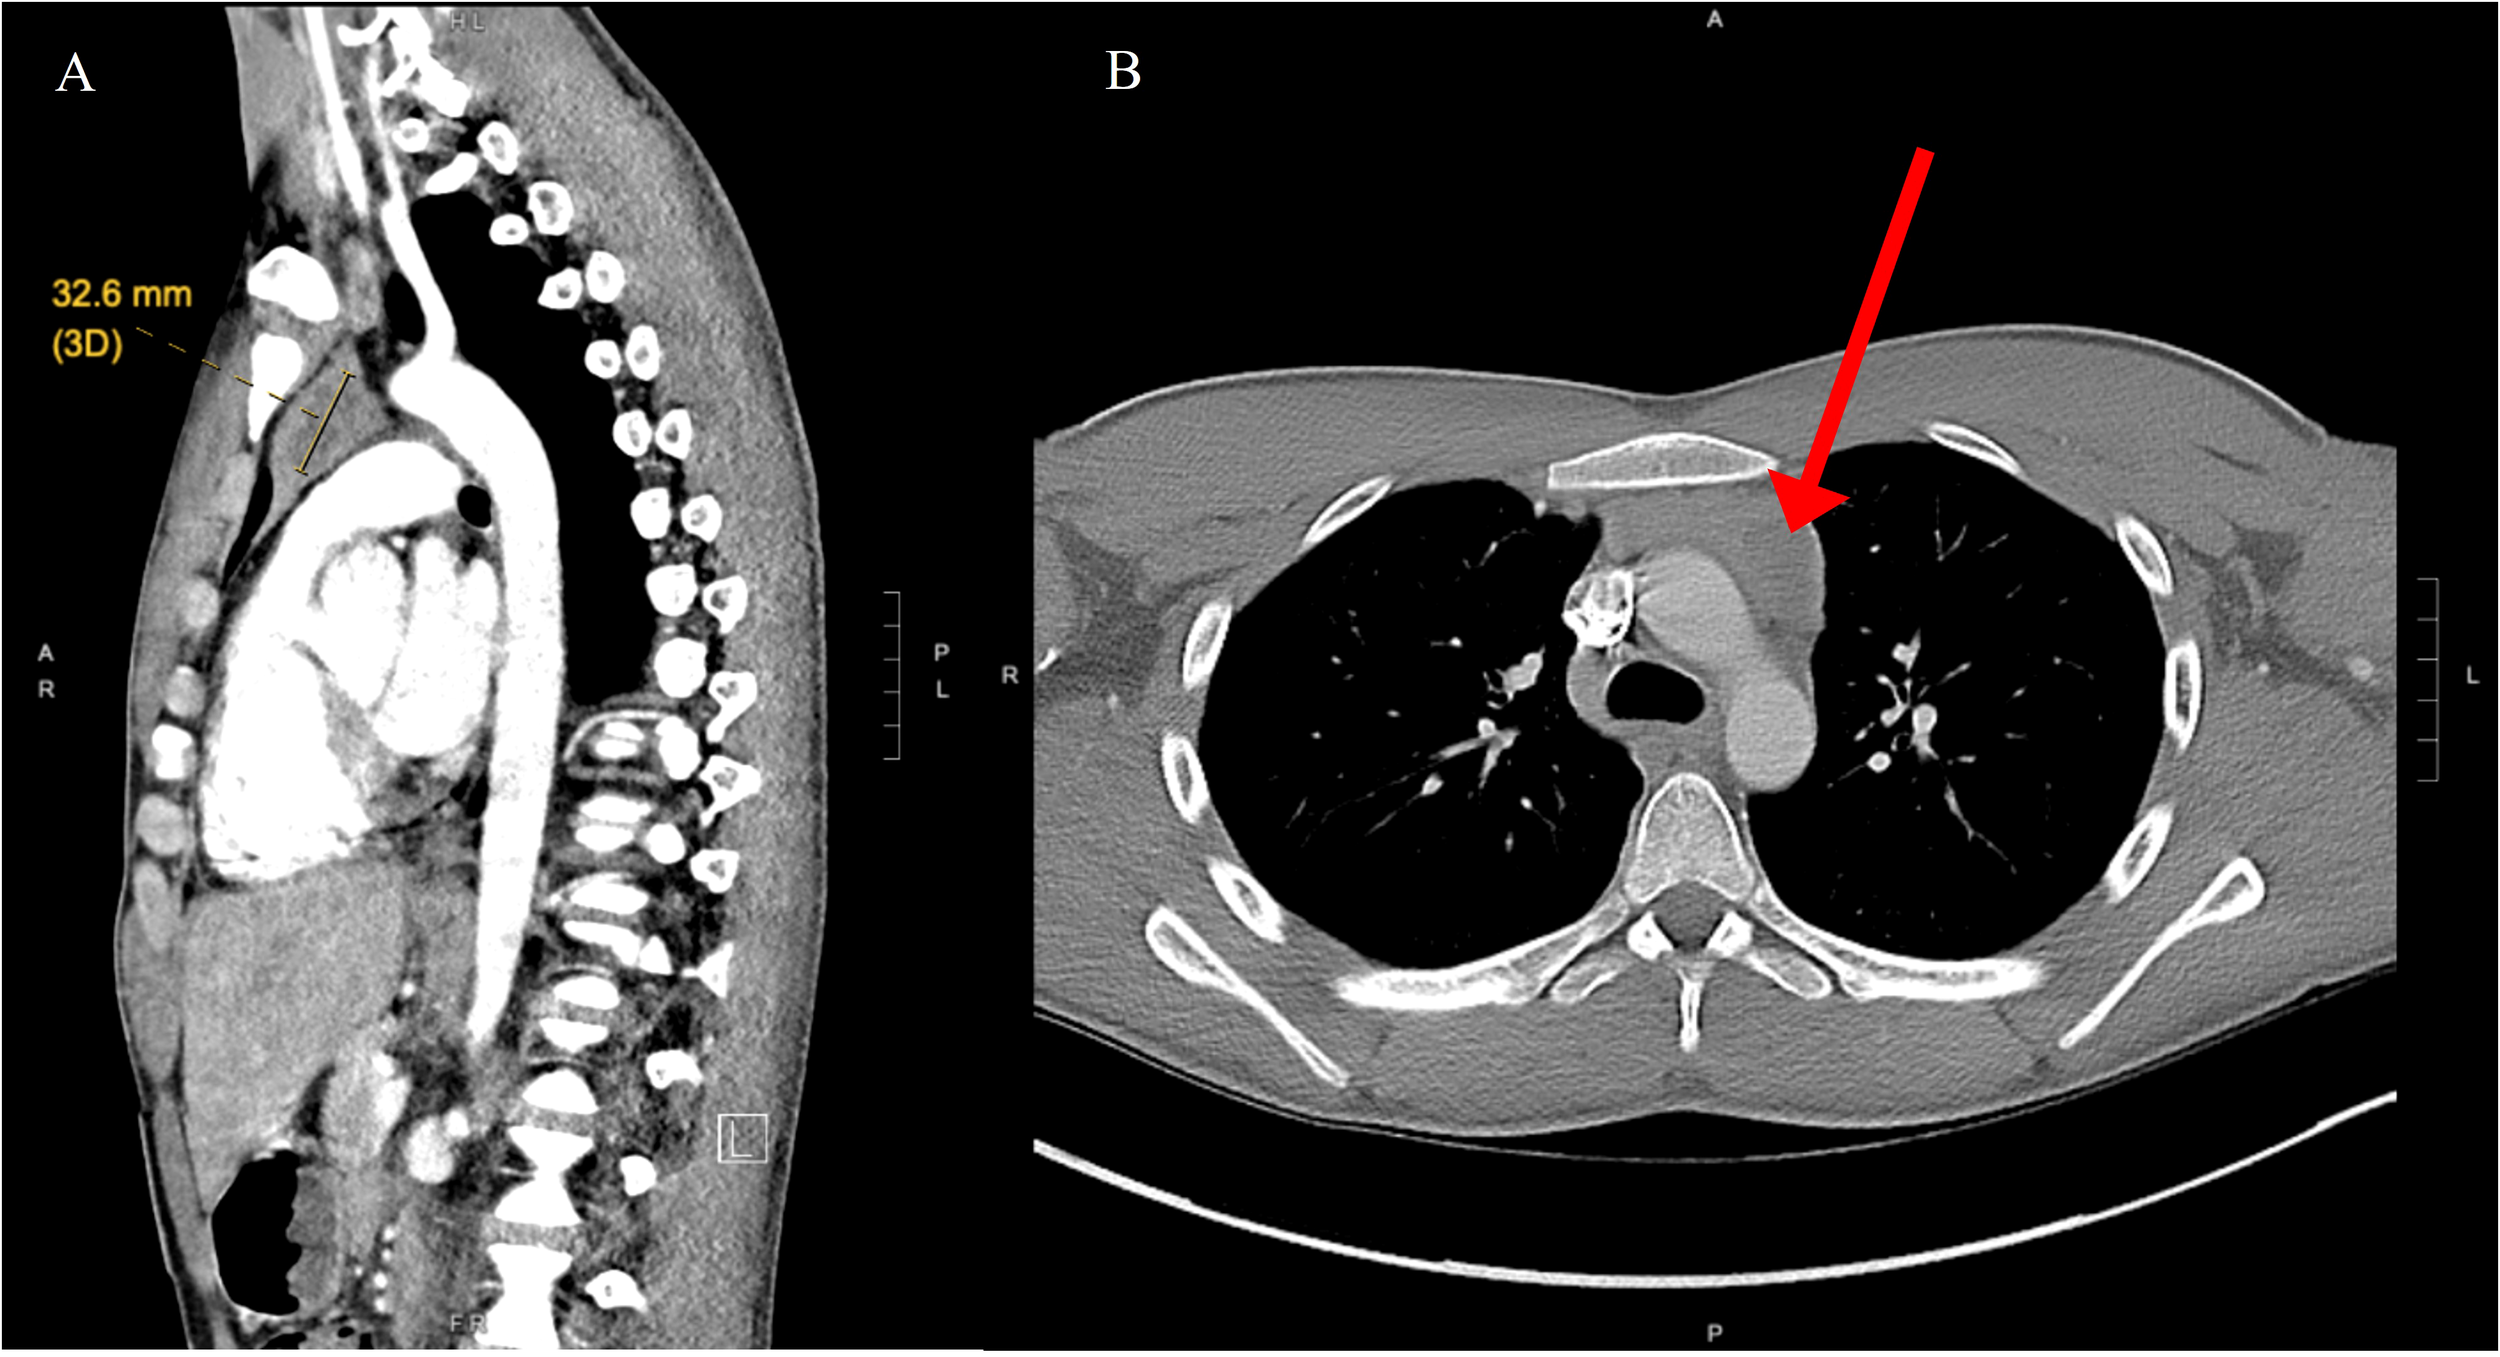

A 19-year-old male with no significant past medical history presented with a chief complaint of hearing loss. Initial otolaryngology work-up revealed severe bilateral sensorineural hearing loss, and he was fitted with hearing aids. Shortly thereafter he began to experience progressive dizziness, neuropathy, ataxia, hand tremor, and generalized seizures. He had no family history of testicular cancer. No past medical history of Klinefelter syndrome. Physical exam was significant for symptoms of cerebellar impairment, including wide-based gait with varying stride length, and prolonged finger-to-nose testing. Extensive work up was performed including serum neoplastic antibody panel: ANNA1 (Anti-Hu), ANNA2S (Anti-Ri), ANNA3S, P/Q-type Calcium Channel, CRMP-5-IgG, PCA2, PCA1,PCA-TR, Neuronal Voltage-Gated K+ Channel, AGNA-1, Amphiphysin, MOGFS Myelin Oligodendrocyte Glycoprotein (MOG-IgG1), NMO/AQP4 FACS, and Muscle-Specific Kinase (MuSK) were normal except Anti-Hu (titer: 1:3840); tumor markers: serum beta-hCG, and alpha fetoprotein were normal. LDH also was within normal limits at 196 (normal 116 – 250). No lumbar puncture or CSF studies were performed, as antineoplastic antibodies were detected prior to procedure. Computed tomography (CT) head with contrast was unremarkable. Magnetic resonance imaging (MRI) head performed with and without IV contrast demonstrated midline cerebellar atrophy. No restricted diffusion noted on MRI. No mass lesions noted. Video electroencephalogram performed was normal without evidence of epileptiform activity. CT chest with contrast revealed a heterogeneous anterior mediastinal soft tissue nodule located within the thymus (Figure 1). Initial CT-guided core mediastinal mass biopsy demonstrated findings suggestive of thymic neoplasm. Subsequently, the patient underwent median sternotomy with radical thymectomy. Pathology revealed seminoma with lymphoid hyperplasia and cystic change with IHC positive for pancytokeratin, CD117, octomer-binding transcription factor 3/4 (Oct3/4), placental alkaline phosphatase (PLAP), and spalt like transcription factor 4 (SALL4) (Figure 2). He was diagnosed with rhombencephalitis, paraneoplastic syndrome secondary to PMS. CT abdomen/pelvis was completed for staging and did not demonstrate any evidence of malignancy or metastatic disease. He was given intravenous (IV) methylprednisolone with mild improvement in his neurological symptoms. He is currently undergoing intravenous immune globulin (IVIG) treatment for his rhombencephalitis. No reported seizures and his neuropathy remains stable. Regarding his cancer, he is under surveillance as his repeat post-operative CT chest did not identify any new suspicious nodules and tumor markers were normal. He works with physical and occupational therapists and is now able to walk with walker (Figure 3).

Figure 1

(A) Nodular area with central low density in the left side of the thymus, measuring roughly 32 mm long axis indicative of mediastinal seminoma (yellow indicator). (B) Computed tomography of axial chest demonstrates anterior mediastinal mass (red arrow).